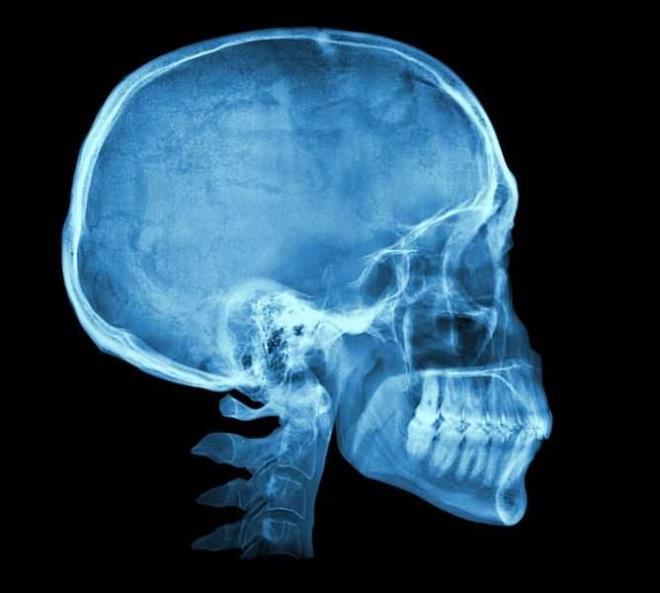

X- IŞINLARI

Bir fizikçi, tüp deneyi sırasında elinin kemiklerinin gölgesini fark etti. Bu da ne böyle? dedi ve tıp dünyası aydınlandı. Kaza, insan vücudunun içini görünür kıldı.